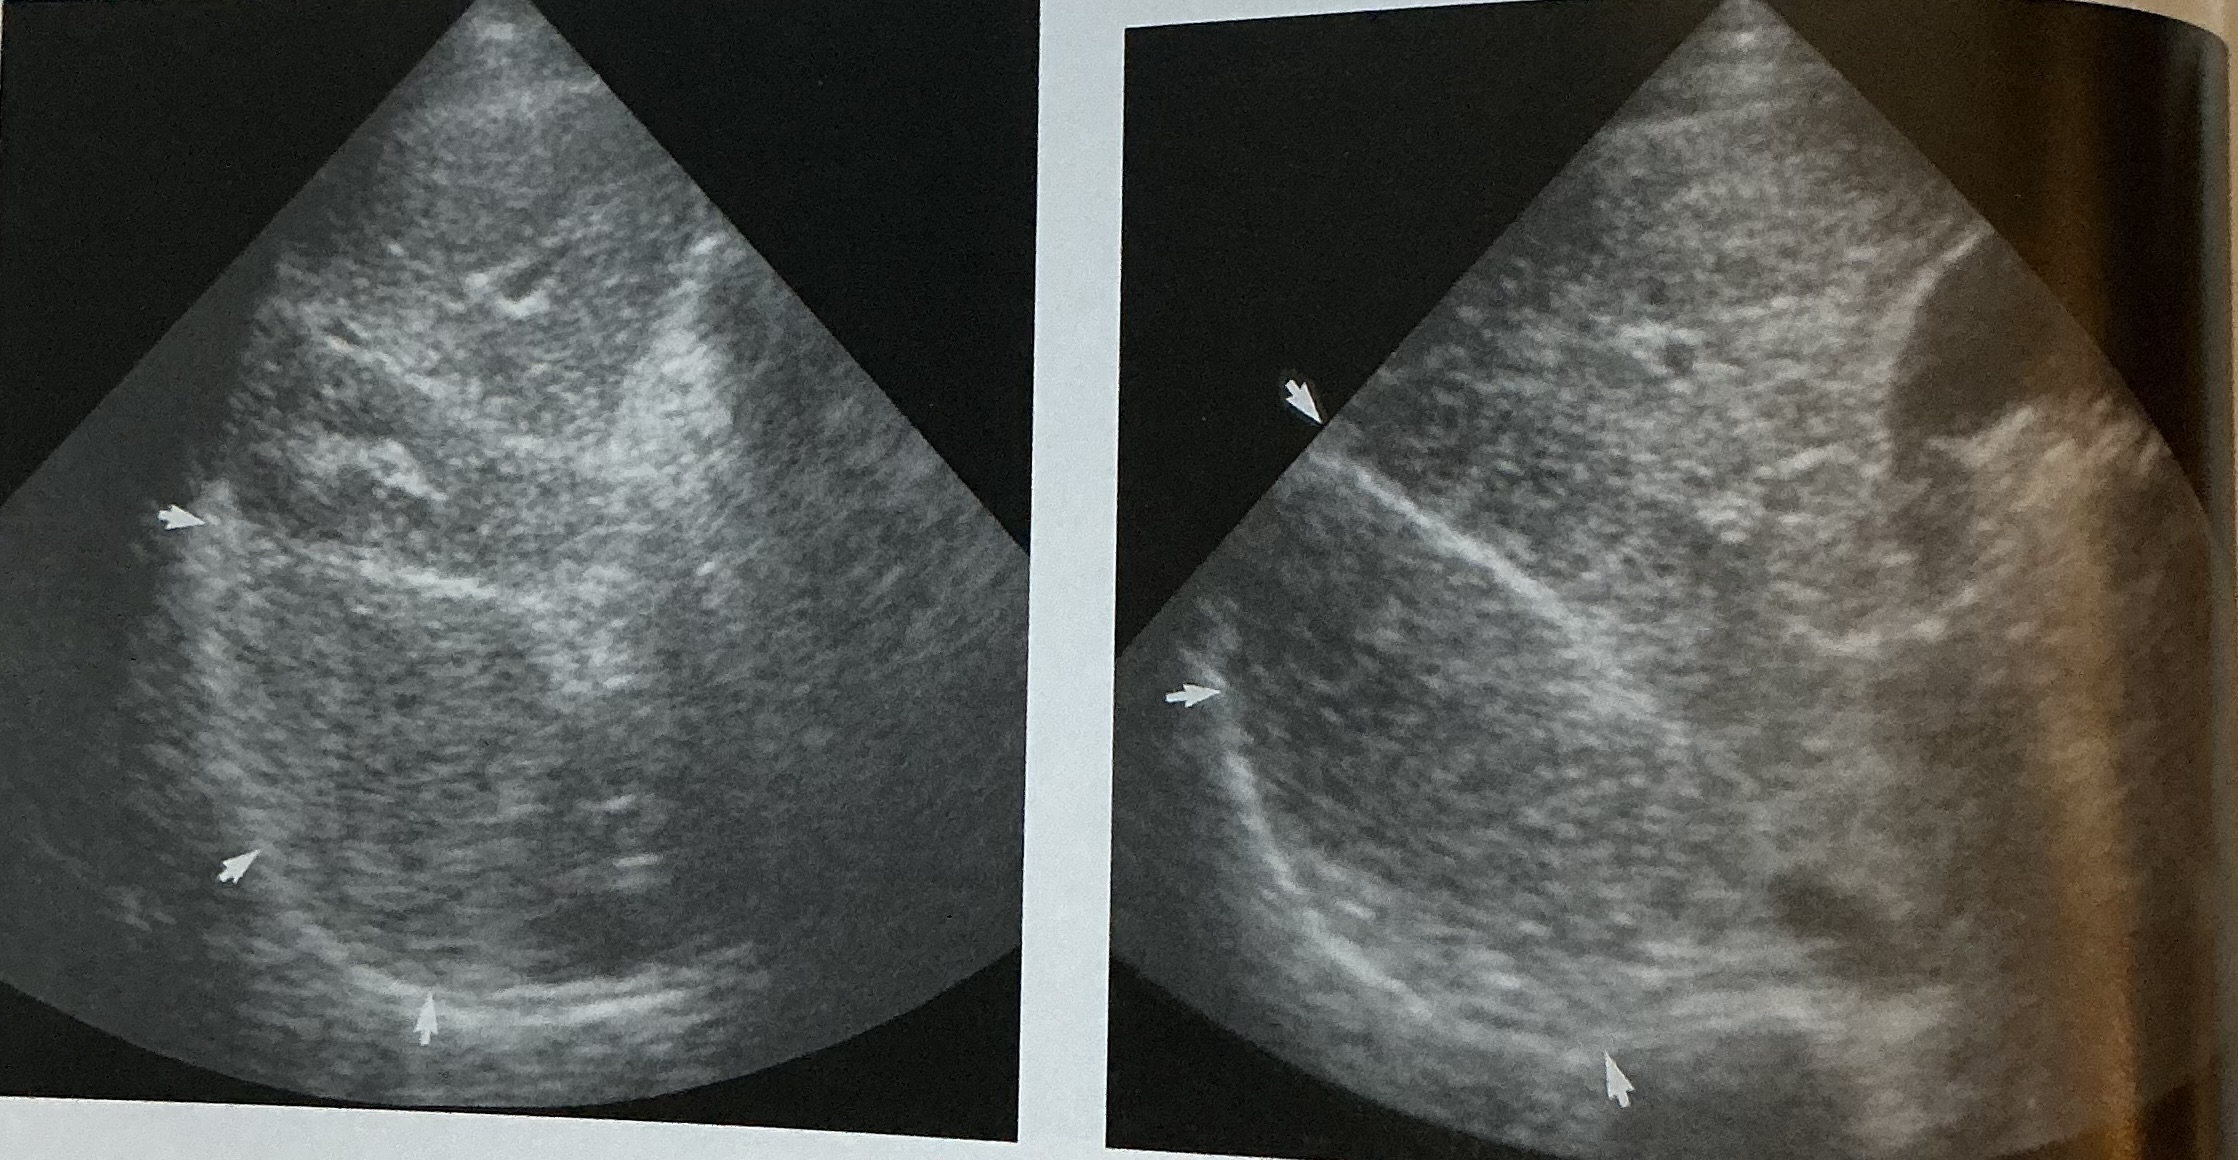

What is this sign? In what disease does this happen?

Starry star sign

acute hepatitis